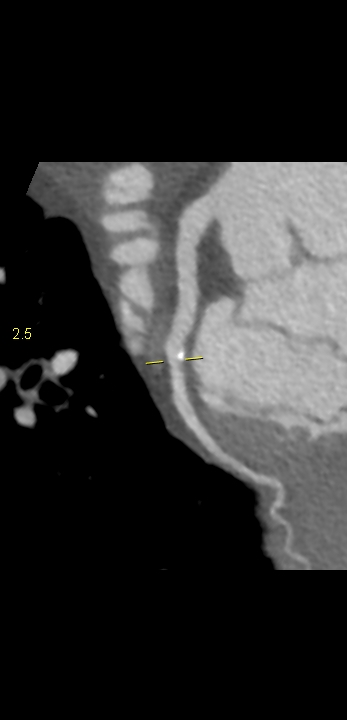

Figururile 1-9: reconstrucție în axul lung al vasului pentru arterele coronare cu evidențierea unui calibru global crescut la nivelul acestora și cu încărcătură ușoară-moderată de placă în principal calcificată

Discuţie caz nr 132: Examinările coroCT se efectuează în principal pentru aprecierea încărcăturii de placă precum și pentru evidențierea reducerilor de lumen ce necesită tratament. Această examinare a evidențiat creștere globală a calibrului arterelor coronare și o încărcătură ușoară-moderată cu placă în principal calcificată, fără a se evidenția arii de stenoză.

DE LUAT ACASĂ!!! Ectazia coronariană este o afecțiune rară caracterizată prin dilatarea anormală (diametrul vasului este de 1.5 ori mai mare) a arterelor coronare, care poate duce la afectarea fluxului sanguin și la un risc crescut de ischemie. Etiologia nu este cunoscută iar afecțiunea poate fi asociată cu ateroscleroză sau factori congenitali și reprezintă o provocare atât în diagnostic, cât și în tratament. Simptomele se suprapun adesea cu cele ale altor boli coronariene, ceea ce face ca identificarea timpurie să fie crucială. Opțiunile de tratament variază de la tratamentul medical cu terapie antiplachetară sau anticoagulantă până la proceduri intervenționale, cum ar fi angioplastia sau intervenția chirurgicală, în funcție de severitatea și riscul de complicații. Tratamentul pe termen lung se concentrează pe prevenirea evenimentelor ischemice și pe abordarea cauzelor care stau la baza acestora.